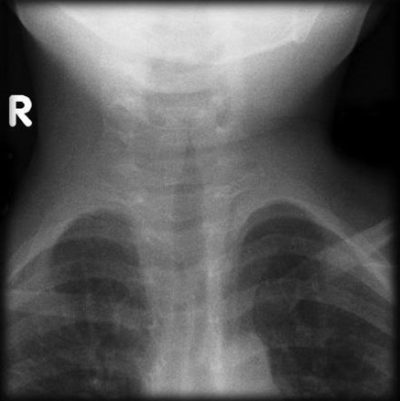

Features seen?

Features seen